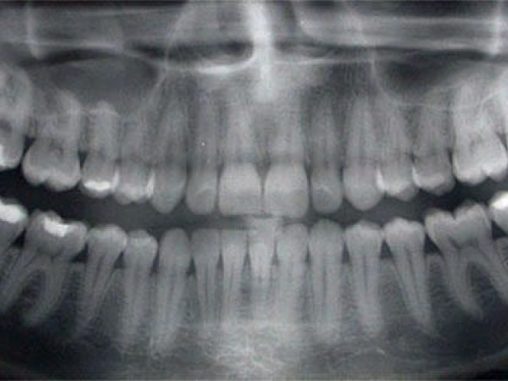

Panorámaröntgen: teljes fogazatról készít felvételt